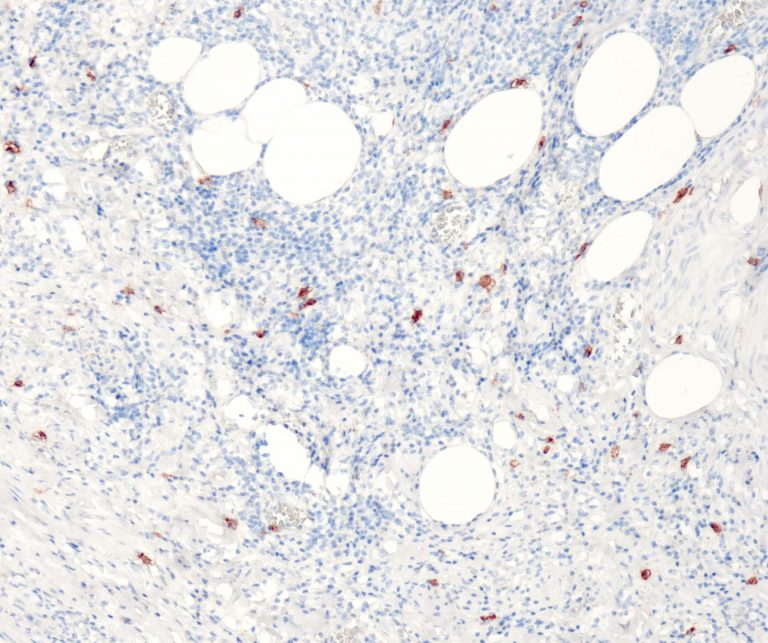

Vascular Pathology

Gastrointestinal (GI) Pathology

General Marker

Breast Pathology

Endocrine Pathology

Gynecological Pathology

Neuropathology

Infection Markers

Lung Pathology

Urinary Tract Pathology

Transplantation Pathology

Soft Tissue Pathology

Hematopathology